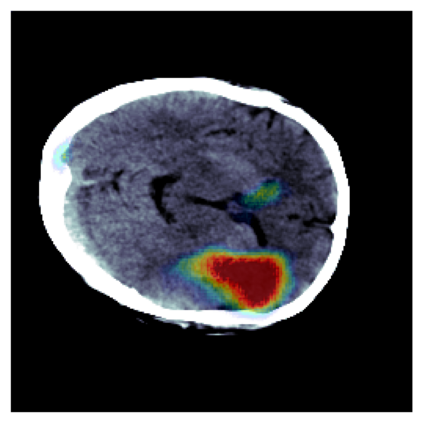

The sigmoid activation is the standard output activation function in binary classification and segmentation with neural networks. Still, there exist a variety of other potential output activation functions, which may lead to improved results in medical image segmentation. In this work, we consider how the asymptotic behavior of different output activation and loss functions affects the prediction probabilities and the corresponding segmentation errors. For cross entropy, we show that a faster rate of change of the activation function correlates with better predictions, while a slower rate of change can improve the calibration of probabilities. For dice loss, we found that the arctangent activation function is superior to the sigmoid function. Furthermore, we provide a test space for arbitrary output activation functions in the area of medical image segmentation. We tested seven activation functions in combination with three loss functions on four different medical image segmentation tasks to provide a classification of which function is best suited in this application scenario.